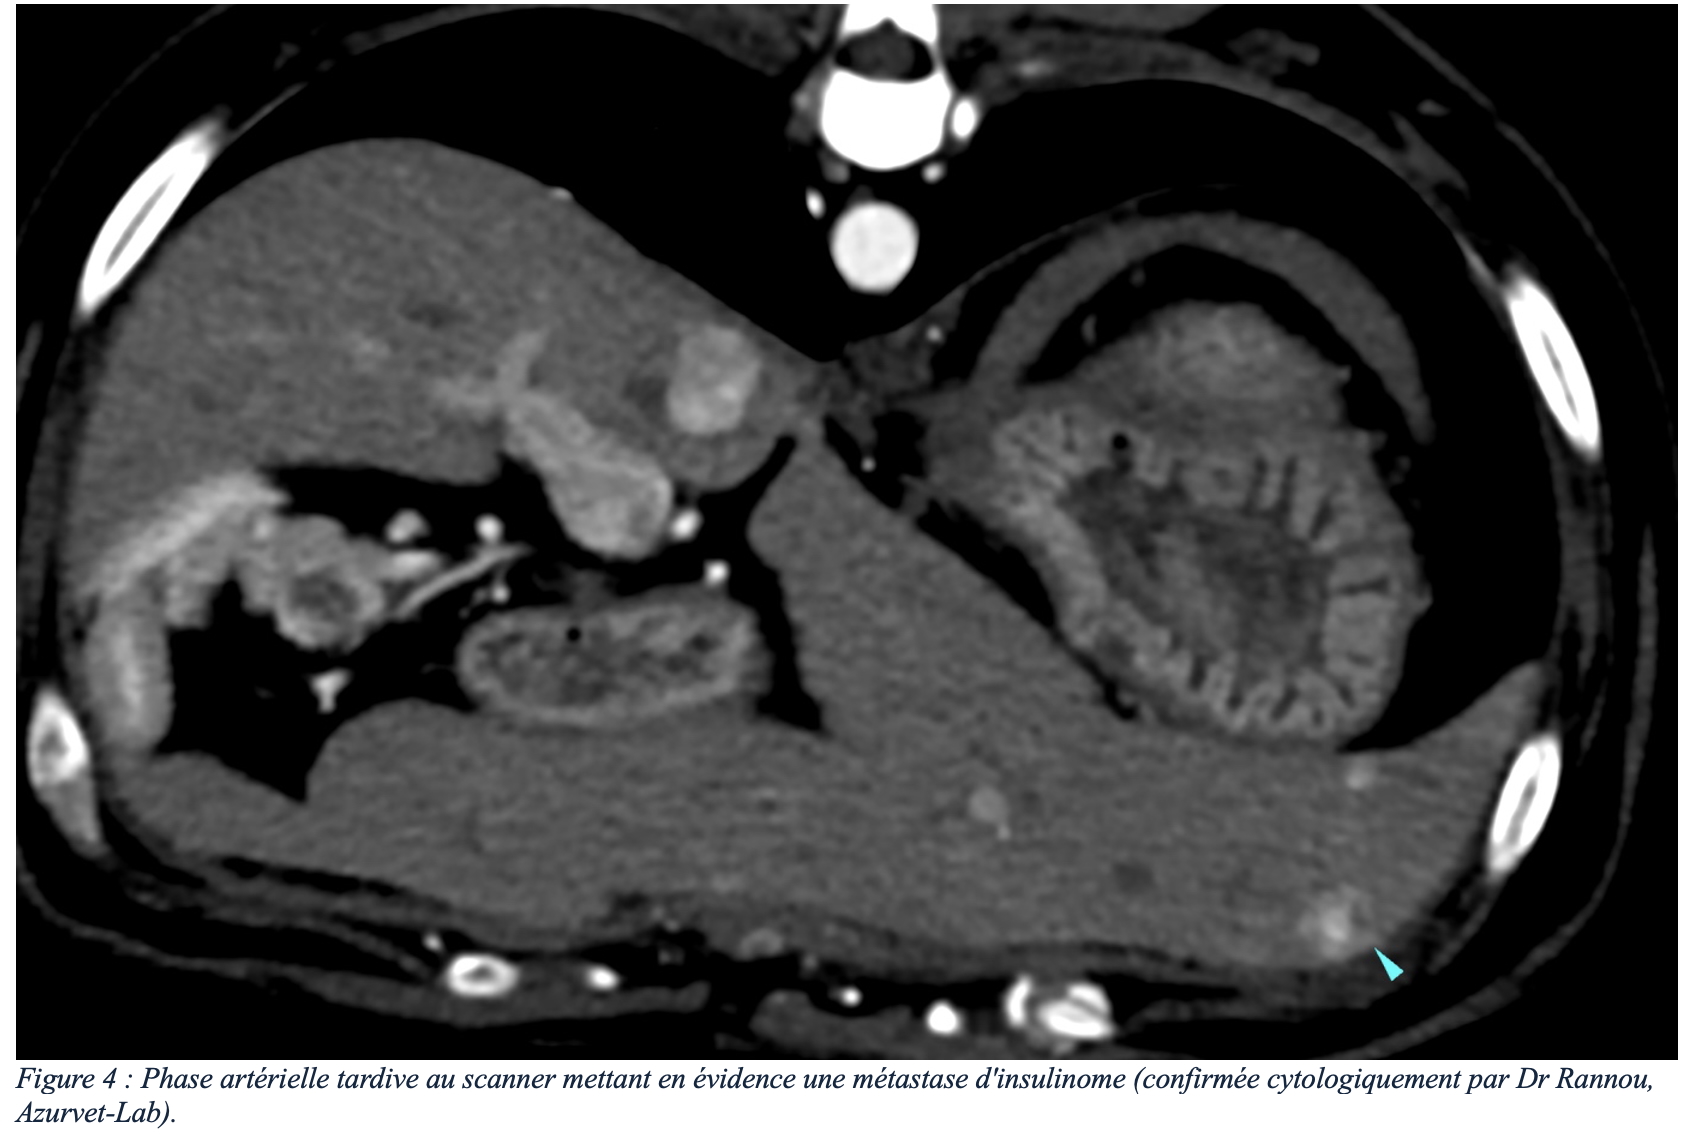

Le scanner, et plus particulièrement la phase artérielle tardive d’un angioscanner (3) (figure 2), est un examen présentant une sensibilité nettement supérieure à l’échographie (4). En effet, les insulinomes et leurs métastases présentent un rehaussement intense et précoce après injection intraveineuse de contraste iodé, permettant une détection plus fiable des insulinomes et leurs éventuelles métastases (bien que des faux positifs soient possibles), tout en s’affranchissant des limites liées au gabarit de l’animal (figures 3 et 4). Les angioscanners peuvent être effectués manuellement, mais les injecteurs automatiques de contraste facilitent la partie technique de cet examen (figure 5).